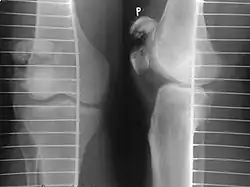

The patella can break in various ways depending on the way it is injured, and into two or more pieces.[1] Types include transverse, the most common, with one fracture line;[5] marginal; osteochondral; and the rare vertical type, or stellate, where a direct compression force gives rise to a comminuted pattern.[5][7] Patella fractures can be further classified as displaced, where the broken ends of bone do not line up correctly and separate by more than 2mm, or undisplaced and stable where pieces of bone remain in contact with each other.[1][7] If fragments of patella bone stick out from the skin it is known as an open patella fracture, and closed if the overlying skin is intact.[1]